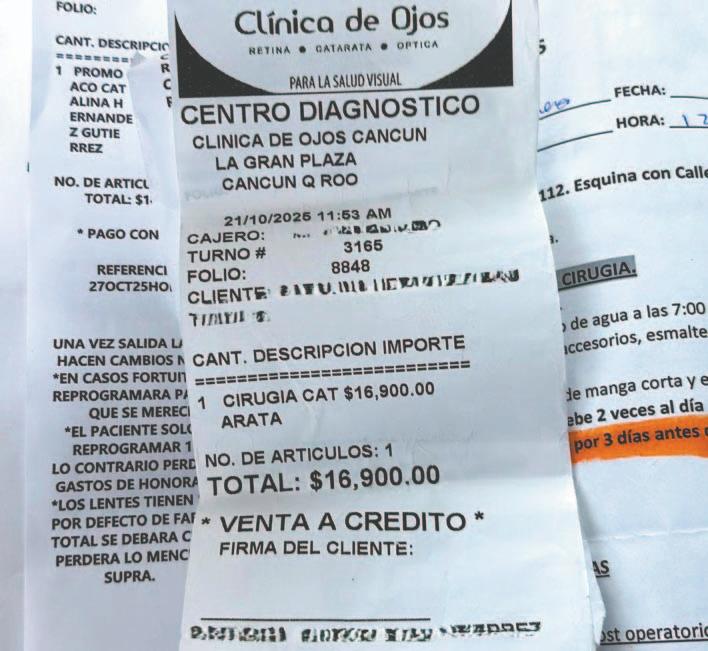

unas 20 familias que tenían programadas cirugías oftálmicas pagaron 300 mil pesos

CANCÚN.- Una clínica oftalmológica fue acusada de presuntamente defraudar a por lo menos 20 familias que ya tenían programadas cirugías oculares.

Los afectados aseguran haber pagado en conjunto más de 300 mil pesos, sin que el dinero fuera registrado por la empresa.

De acuerdo con los quejosos, realizaron pagos constantes en la sucursal ubicada en la Gran Plaza hasta sumar alrededor de 16 mil 900 pesos por persona. La cirugía se llevaría a

cabo el lunes pasado en otra clínica de la misma empresa, situada en la avenida Cobá.

Locatarios informaron que el establecimiento no abrió ayer, a pesar de que normalmente labora a diario.

Añadieron que desde el lunes observaron movimientos inusuales, ya que el local abrió hasta la tarde y personal de la Procuraduría Federal del Consumidor (Profeco) acudió acompañado de guardias.

Aunque la visita no pasó a mayores, la clínica no ha vuelto a abrir.

La sorpresa para los pacientes llegó cuando acudieron a confirmar sus cirugías y se enteraron de que el dinero entregado en la sucursal de la plaza nunca fue registrado.

Según testimonios, al menos 20 familias fueron víctimas del mismo esquema, lo que representa un perjuicio económico de 338 mil pesos. Los afectados mostraron comprobantes de pago con el logotipo oficial de la Clínica de Ojos; sin embargo, el responsable del establecimiento les informó que la empresa

CANCÚN.- Habitantes de la Supermanzana 91 exigieron a Aguakan reparar una fuga de aguas residuales que, aseguran, lleva varios días sin atención y cuyo olor se ha vuelto insoportable.

no se haría cargo, argumentando que nunca recibió esos recursos.

Ante la falta de respuesta, los pacientes acudieron a la Profeco, donde -aseguraron- fueron ignorados y les informaron que no podían hacer nada al respecto.

Algunos familiares optaron por volver a pagar los casi 17 mil pesos para no retrasar los procedimientos, debido a que su salud visual se deterioraba con el paso de los días. Otros decidieron acudir a la Fiscalía General

del Estado para interponer una denuncia penal por fraude. No es la primera vez que esta empresa se ve envuelta en polémicas. Años atrás, pacientes denunciaron haber sufrido infecciones presuntamente provocadas por un químico utilizado durante los procedimientos. Además, en sus redes sociales se observan múltiples comentarios de usuarios que los acusan de presuntas estafas y malas prácticas.